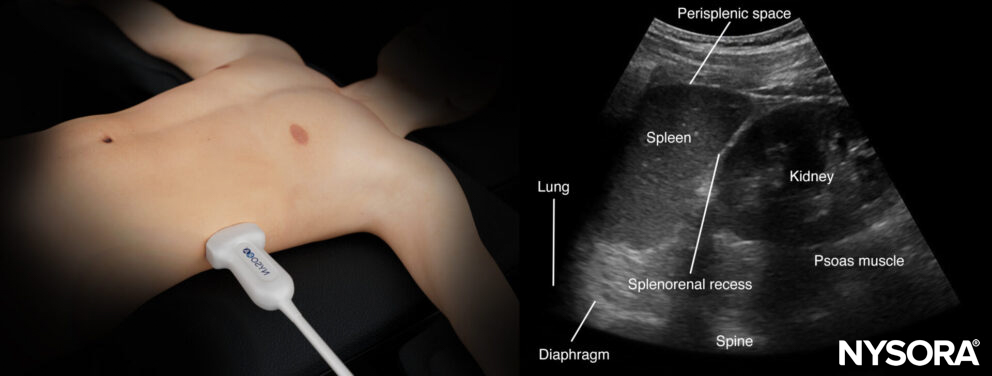

Left upper quadrant (LUQ)

This view allows free fluid assessment in the left thorax and abdomen.

- Position the transducer on the posterior axillary line in the LUQ with the orientation marker toward the head of the patient.

- Start scanning caudally until you visualize the spleen and the kidney.

- Structures of interest: lung, diaphragm, spleen, perisplenic space, kidney

Normal sonoanatomy:

Ultrasound anatomy of the left upper quadrant and relevant anatomical structures.

Reverse Ultrasound Ultrasound anatomy of the left upper quadrant and relevant anatomical structures.